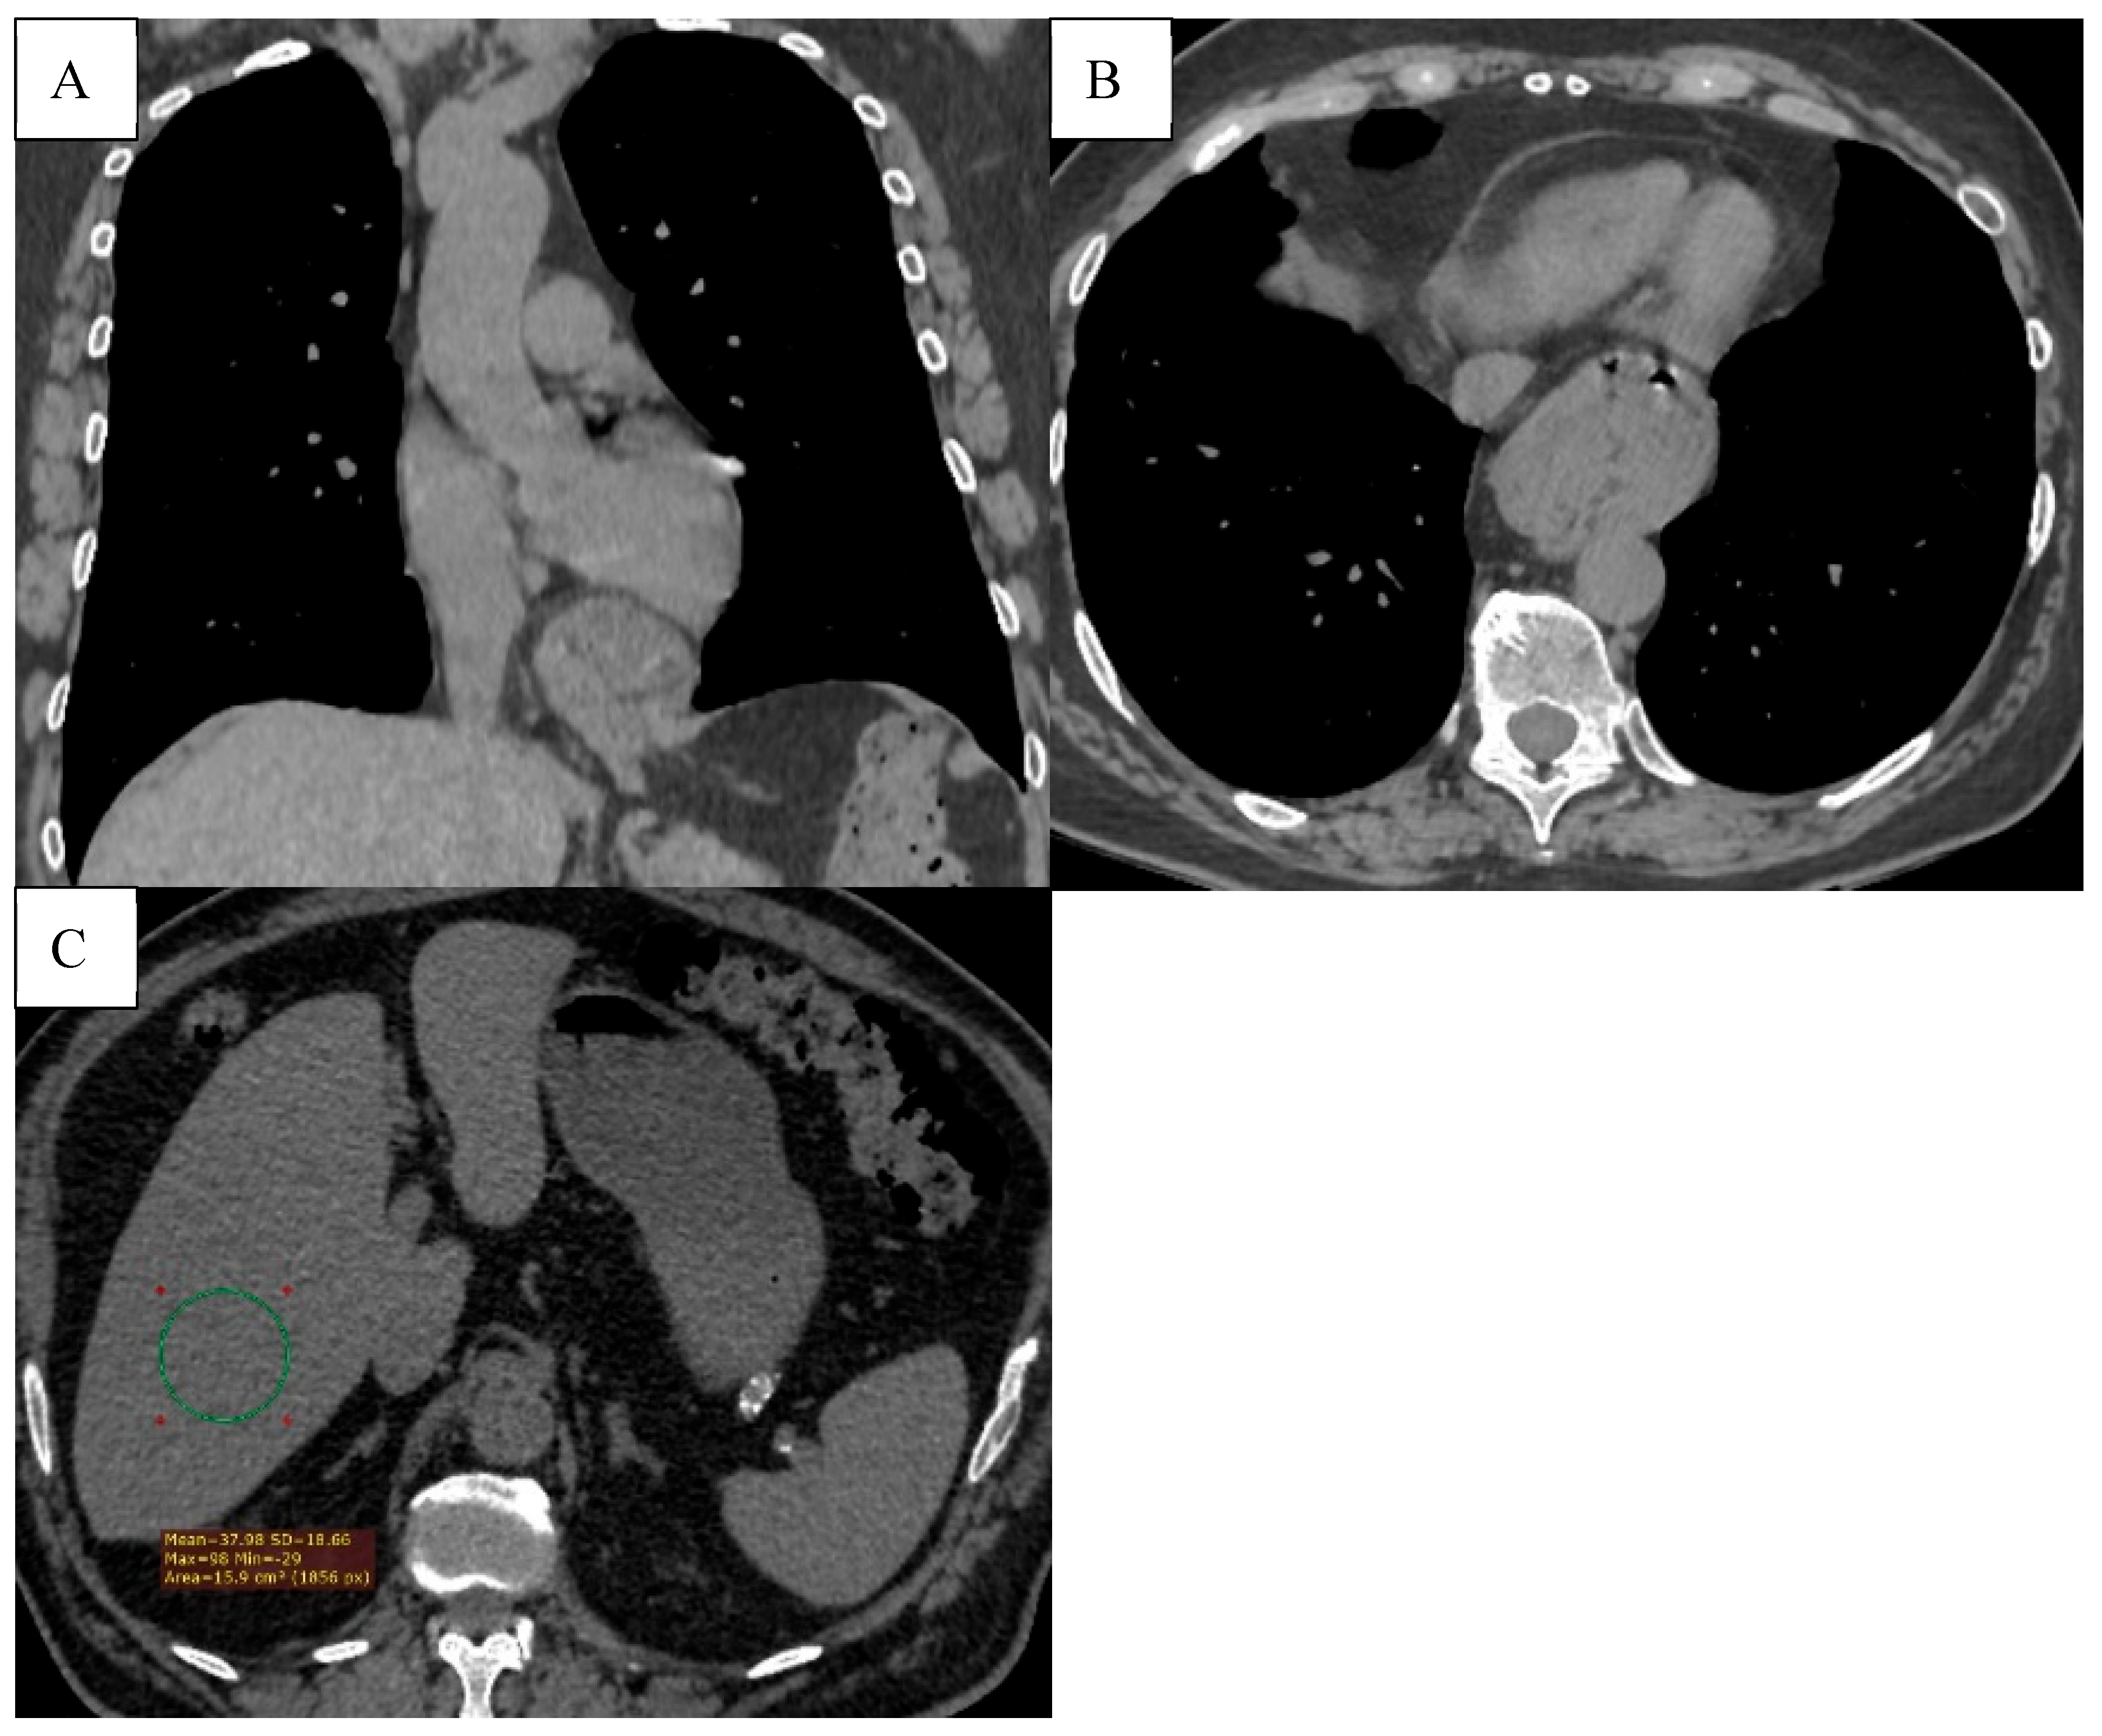

As depicted in Figure 6, chest CT further revealed a wide spectrum of comorbidities, including bronchiectasis, pulmonary artery enlargement, osteoporosis, and interstitial lung disease.

As demonstrated in Figure 8, HRCT also revealed extrapulmonary changes, including hiatal gernia and hepatic steatosis, further supporting the systemic nature of COPD.

Figure 6. (A) Bronchiectasis (multiple types of bronchiectasis in the lower lobe of the right lung, some with mucoid impaction). (B) CT signs of pulmonary hypertension (diameter of the pulmonary trunck 3.8 cm (normal < 2.9cm). (C) Osteoporosis, bone density measurement at the level of L3 (86.96 HU). (D) ILD (Interstitial Lung Disease), subpleural honeycombing formed by clustered cysts stacke together in several layers. Reticular pattern. Left pleural effusion.

Figure 8. (A) The axial CT scan shows a hiatal hernia (type 1), with a part of the stomach protruding through the esophageal hiatus into the thoracic cavity. (B) Hepatic steatosis. Diffusely decreased liver attenuation (37.98HU).